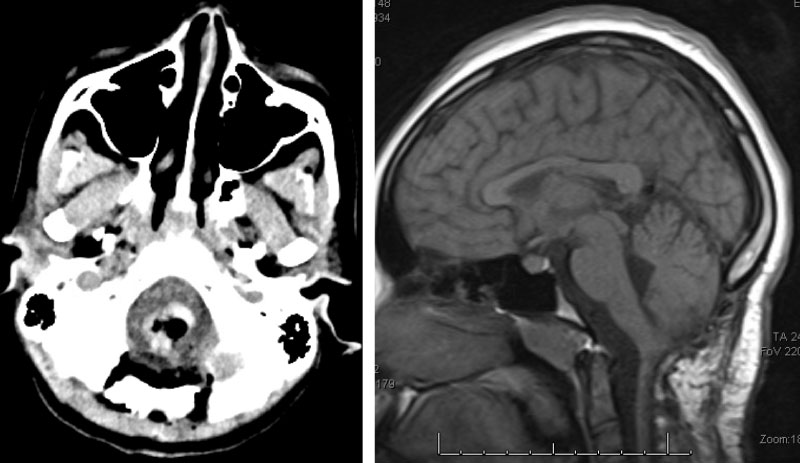

Figure 1. Brain MRI showing tumor mass (TM) with cystic component (CC) and edema (T2-weighted MRI, left) in the lower brainstem and upper cervical cord. Mass with contrast enhancement (post-contrast T1-weighted MRI, middle and right).

A teenage boy presented with 6 months of weight loss and difficulty swallowing. A contrast-enhancing mass in the brainstem and upper cervical cord was found which was suspicious of a symptomatic hemangioblastoma (Figure 1).